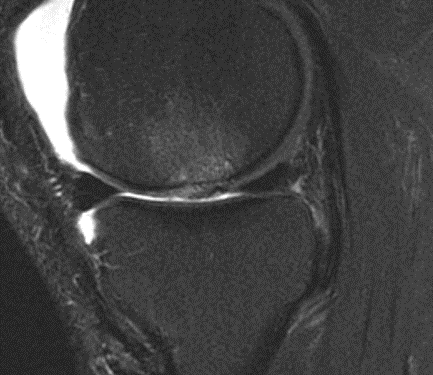

MRI 6 months after cartiform

MRI 12 months after cartiform